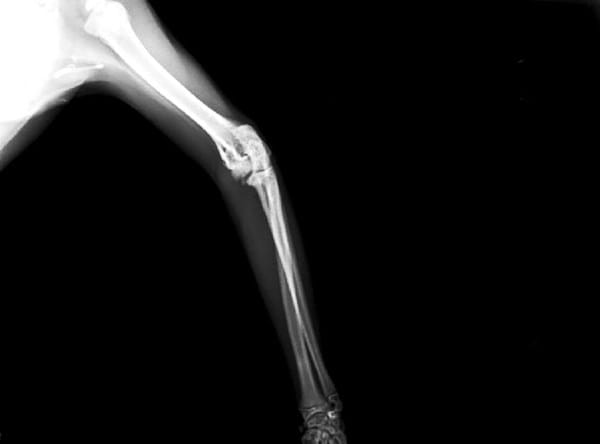

A mi gata de año y medio le han diagnosticado artrosis de cadera y artrosis de codo, también fue diagnosticada con calicivirus hace unos meses. El veterinario que la ha diagnosticado nos aconseja que NO la operemos, y nos recomienda dos opciones de tratamiento: aplicar factores de crecimiento o trasplante de células madre.

El pronóstico que nos ha dado no es demasiado bueno, puesto que el codo izquierdo ya está en bastante mal estado como se ve en las radiografías y las caderas van por el mismo camino, sobretodo la derecha. Además nos comentó que el calicivirus va a hacer que se deteriore todo más rápido.